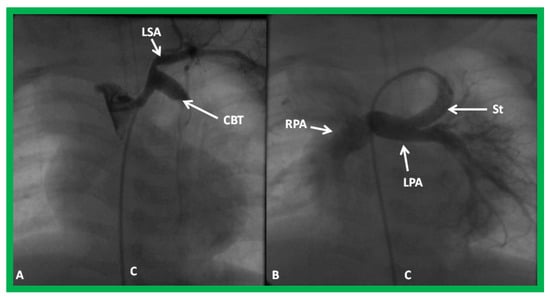

Babies with a completely obstructed shunt manifest with marked cyanosis and respiratory distress. A continuous murmur of the shunt that was present previously is no longer heard on auscultation or is markedly decreased in intensity. The management of an obstructed shunt includes use of principles of basic life support, namely, the airway, breathing, and circulation (or circulation, airway, breathing as per the new protocol) with intubation, as necessary, and starting cardiopulmonary resuscitation. In babies with suspected shunt blockage, heparin should be administered to prevent futher progression of the thrombus. Concurrently, stat echocardiogram should be performed, and pediatric cardiology and cardiovascular surgical consultation should be obtained promptly. Transcatheter recanalization of the shunt (Figure 27) in an urgent manner is feasible by interventional pediatric cardiologists [58,87,100] or the shunt may be revised, or the baby placed on ECMO by pediatric cardiovascular surgeons, depending upon the baby’s clinical status and institutional preference. The shunt thrombosis appears to occur, though infrequently, despite the routine use of platelet inhibiting drugs such as aspirin in an attempt to avert such a problem.

Figure 27.

Selected cineangiographic frame demonstrating clotted Blalock-Taussig (CBT) shunt (A). After unsuccessful recanalization with mechanical thrombolysis and balloon angioplasty, a stent (St) was implanted (B). Angiography with tip of the catheter (C) in the proximal portion of the stent showed complete opening of the BT shunt with visualization of right (RPA) and left (LPA) pulmonary arteries. LSA, left subclavian artery. Reproduced from Reference [61].

Stenotic shunts without acute symptoms may undergo electives balloon angioplasty or stent implantation across the stenotic BT or Sano shunts (Figure 28 and Figure 29).